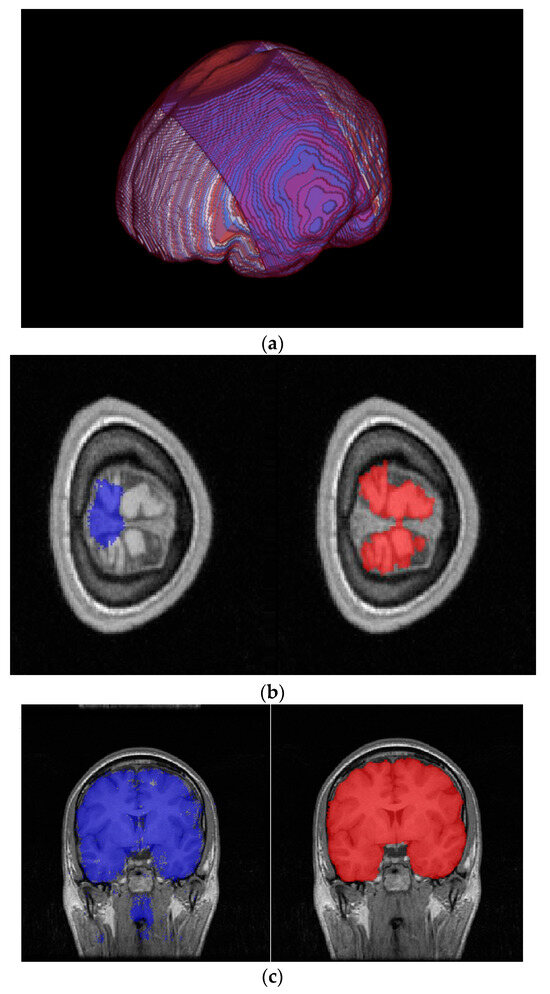

3.2. Results